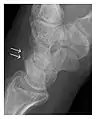

Occult osseous injuries may result from a direct blow to the bone by compressive forces of adjacent bones against one another or by traction forces during an avulsion injury. Lesions in the tibial plateau, hip, ankle, and wrist are often missed. In a tibial plateau fracture, any disruption of the posterior and anterior cortical rims of the plateau should be sought. Impaction of subchondral bone will appear as an increased sclerosis of the subchondral bone (Figure 1). In the hip, posterior acetabular fractures also present subtle radiographic findings. The acetabular lines should then be carefully examined keeping in mind that the posterior rim, which is harder to see on X-rays, is more frequently fractured than the anterior rim (Figure 2). In the wrist, detection of carpal bone fractures is often challenging, with up to 18% of scaphoid fractures radiographically occult. Carpal fractures, especially the scaphoid, are associated with the risk of avascular necrosis. In apparently normal wrist radiographs from symptomatic patients, if there is history of a fall on an outstretched hand with pain in the anatomic snuffbox, suggesting scaphoid injury, the initial examination with posteroanterior, lateral, and pronation oblique views must be complemented by other specific views such as supination oblique and the "scaphoid" view A careful examination of cortices for evidence of discontinuity or offset and cancellous bone for lucency is necessary (Figure 3).[1]

Figure 1: A 56-year-old woman presenting with left knee pain after a fall. (a) Initial anteroposterior radiograph was considered normal, however, subtle cortical disruption of the anterior rim of the medial tibial plateau, medial to the tibial spine, is noted (arrow). (b) Coronal T1-weighted MRI confirms the cortical disruption (arrow) and shows extensive fracture through the proximal tibia. (c) Coronal proton density-weighted image with fat saturation shows extensive edema in the subchondral bone. Note also hypersignal adjacent to the medial collateral ligament corresponding to a grade I sprain (arrowheads).[1]